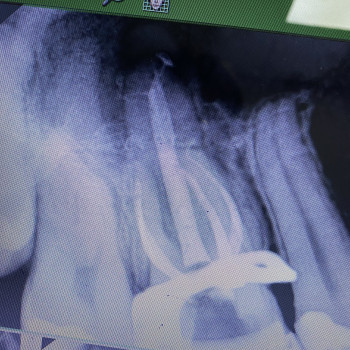

Лікування зубів під мікроскопом. Лікування карієсу, пульпіту, періодонтиту. Лікування захворювань ясен.

Лікування зубів під мікроскопом